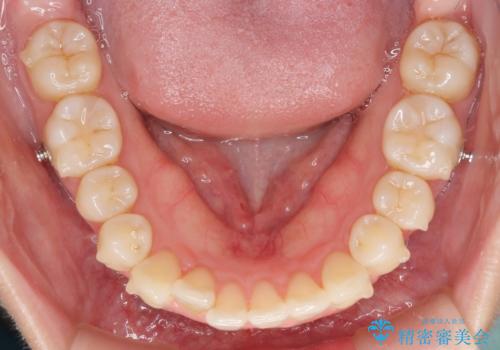

- 上下前歯のデコボコを気にして来院された患者様です。

インビザラインによる上下歯列の側方拡大と後方移動、IPR(歯と歯の間を削る)にるスペースの獲得により歯列を整えることとしました。

1日22時間の装着時間をしっかり守ってくださったので、予定していた1年よりも早く治療を終えることができました。

インビザライン矯正特有の奥歯がしっかりと咬合しない感覚も改善され、大変満足していただきました。